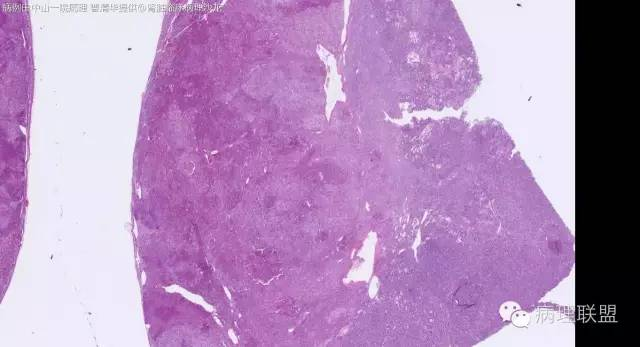

女性,50岁,肾上腺肿物(影像及手术均确认肿物位于肾上腺,界限清楚)。血压升高。(病例由 中山一院病理 曹清华提供,致谢!)

伴假腺样结构的肾上腺皮质腺瘤,合并髓脂肪瘤

从肿瘤的位置及镜下与肾上腺皮质的关系看,应该像是皮质来源肿瘤。假腺样结构的皮质腺瘤没有见过,似乎文献也还没查到。另外inhibina, melanA, syn均阴性(肿瘤旁正常皮质阳)感觉有点迷惑。。。请老师指教,有相关文献么?@武警嘉兴医院 周泉